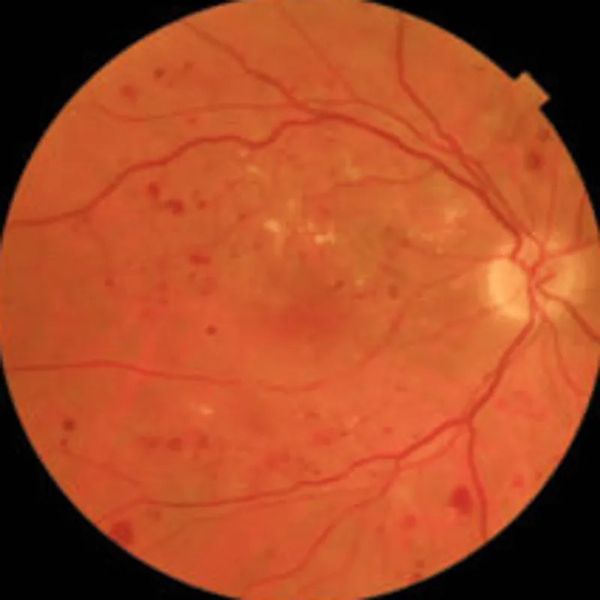

Diabetic retinopathy is a serious eye condition that affects individuals with diabetes and can lead to significant vision loss if not properly managed. It occurs when high blood sugar levels damage the blood vessels in the retina, the light-sensitive layer at the back of the eye. As these vessels weaken and leak, they can cause swelling and bleeding, leading to various stages of retinopathy. Protect your clarity of sight by booking a diagnostic consultation with our specialists to assess your current retinal health.

Diabetic retinopathy can have a profound impact on your vision. As the condition progresses, it can lead to fluctuations in your prescription, increased myopia (nearsightedness), and, in severe cases, even blindness. Early stages may not present noticeable symptoms, but as the disease advances, you might experience blurred vision, dark spots, or difficulty seeing at night.